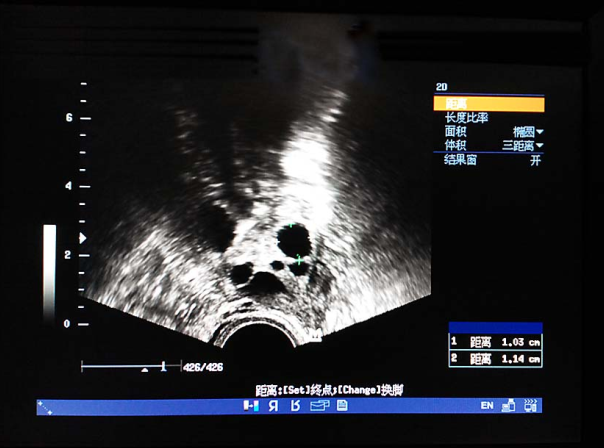

(1)超声检查:推荐使用经阴道超声,明确子宫和卵巢大小、位置、形态、有无异常结节或囊、实性包块回声,评估卵巢储备。还可监测优势卵泡发育情况及同期子宫内膜厚度和形态分型。

卵泡生长发育监测(窦卵泡期) 卵泡生长发育监测(卵泡中期) 卵泡生长发育监测(卵泡晚期)

卵泡生长发育监测(排卵前期) 输卵管积水超声表现 输卵管积水超声表现